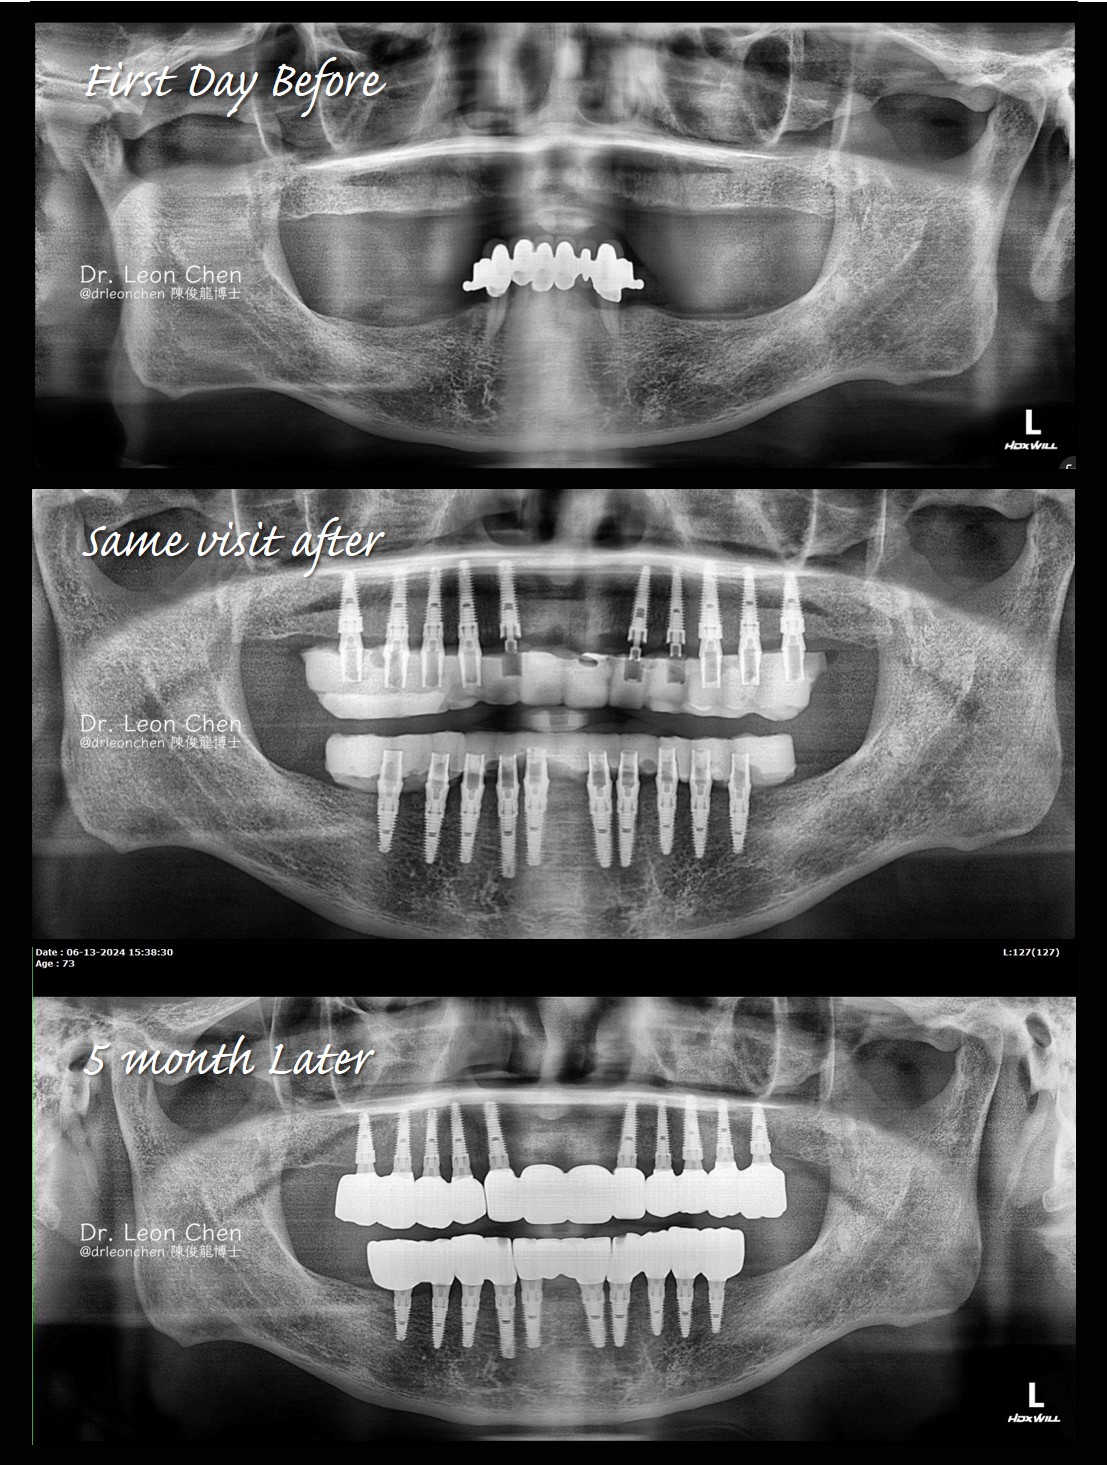

全口植牙的親身見證 Safer and Simpler

陳博士趕到診所會診後立即幫他治療,上顎植10顆、下顎植10顆,也馬上幫他裝上固定臨時牙,從戽斗直接變成接近正常咬合了。

當天晚上就直接去應酬吃飯,他的朋友都不敢相信他剛植完牙過來。五個月後回診裝上永久牙。

整個療程只動一次手術、打一次麻醉,全程free hand手術加臨時固定牙,2小時搞定。

手術時間約40分鐘就結束,旁邊跟診的醫師都覺得幸運,能親眼目睹陳博士的live surgery,這就是「一冠一釘,精奈創一鑽植牙」新觀念與技術的成果,更安全、更簡單。